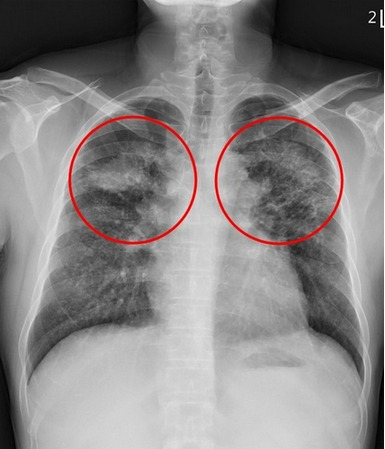

黃先生(化名)自二十一歲至三十歲有長達近十年的磨石工作經歷,雖後續離開此行業,卻在四十四歲時從影像檢查中發現肺部有大塊陰影,後續確診為塵肺症導致的肺部纖維化。「矽肺症最可怕的是,一旦患上,不僅不可逆還將會持續惡化,且沒有特效藥。」劉迪塑醫師說明,吸入的粉塵大多沉積在上肺葉,因發炎反應和局部纖維化而產生許多間質性結節,嚴重時甚至會發展為漸進性大量纖維化,在雙上肺葉形成對稱的腫塊,臨床上需和惡性腫瘤或結核病的腫塊或結節做鑒別診斷。

圖說:劉迪塑醫師指出,矽肺症患者的肺部因發炎反應和局部纖維化而產生許多間質性結節,嚴重時甚至會發展為漸進性大量纖維化,在雙上肺葉形成對稱的腫塊。